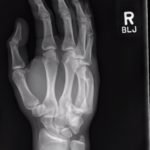

A two-view radiograph of the right hand was obtained which revealed a dorsal dislocation of the distal fourth and fifth metacarpals (see red and blue outline, respectively) with a concomitant fracture of the distal fifth metacarpal (see yellow line) and avulsion fracture of the lateral aspect of the hamate (see green line). After reduction the fourth and fifth metacarpal dislocations are resolved; however, the distal fifth metacarpal fracture (yellow line) and avulsion fracture of the lateral aspect of the hamate (green line) are still visible.

In a case series including 21 patients, dorsal dislocation of carpometacarpal joints was initially missed in 15 of these cases.1 This is often due to the overall swelling that may mask the ulnar deformity as well as failure to obtain a true lateral X-ray.This is a rare injury because there are many strong supporting ligaments.2 The dislocation requires closed reduction, with application of ventral longitudinal pressure and traction of fourth and fifth digit.3 There is debate amongst hand surgeons if closed reduction followed by casting or open reduction is superior, but there have been no large-scale studies comparing treatment options.4 Post-reduction films were obtained and an ulnar gutter splint was placed. The patient was instructed to follow up with hand surgery in the next week.